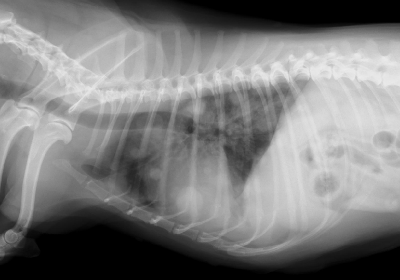

Step 05. レントゲン

上記の検査は、『腫瘍の正体を知るための検査』でした。レントゲンやエコーは、『腫瘍があるかどうか』の検査です。体内の腫瘍を探したり、他の臓器にできた腫瘍が肺転移していないか探したりが目的となります。

手術後の経過チェックとして胸部の撮影をすることもあります。

乳腺腫瘍

悪性の乳腺腫瘍の肺転移です。ワンちゃんを横から撮影した画像です。大小さまざまな白い丸が転移巣です。こうなると残された人生を少しでも快適にするための『緩和治療』が重要となります。